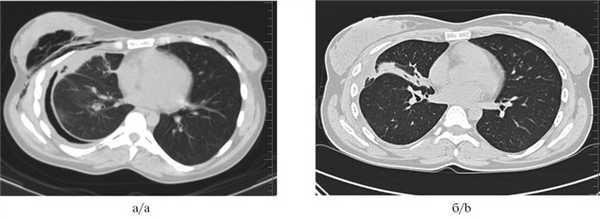

Рис. 3. Мультиспиральные компьютерные томограммы органов грудной клетки до (а) и после (б) установки бронхоблокатора.

а — определяется пневмоторакс справа, массивная подкожная эмфизема, б — через 1 мес после установки бронхоблокатора, пневмоторакс справа разрешен, верхняя доля правого легкого в состоянии ателектаза.